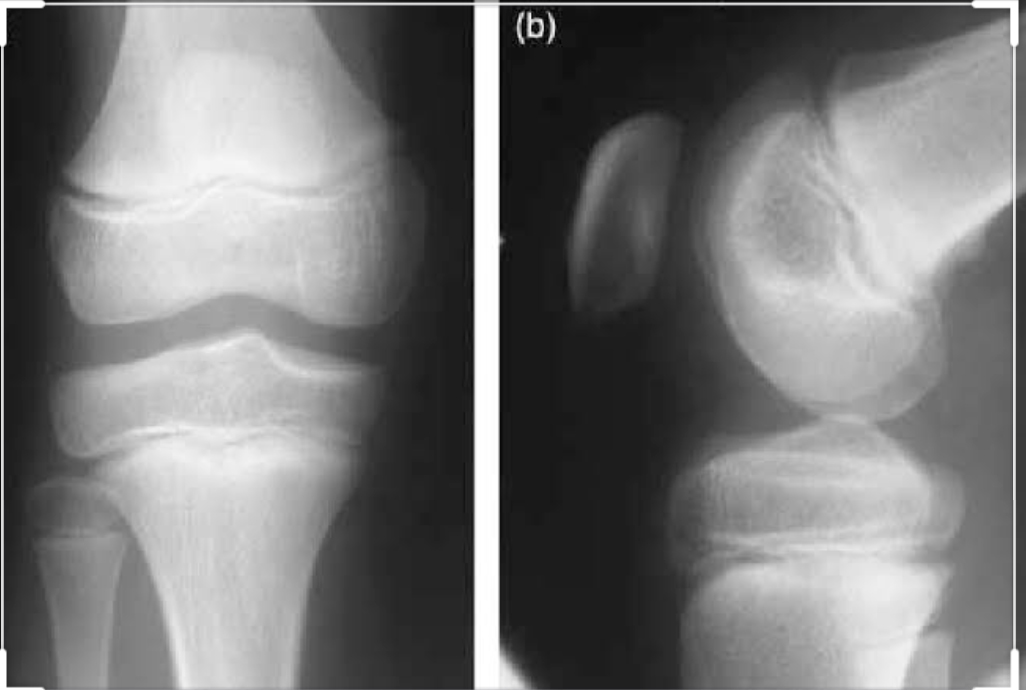

Radiology